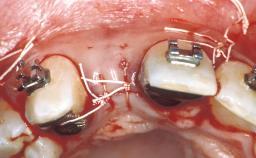

Replacement of Congenitally Missing Upper Lateral Incisors with Narrow Neck Implants, Restored with Ceramo-Metal Crowns, Cemented

A healthy 19-year-old male patient presented at our clinic for a consultation on treatment options to replace the congenitally missing teeth at sites 12 and 22. He expected the treatment to be performed within one year, as he was planning to move away from the area. After a consultation on treatment options, the patient requested an implant-retained fixed restorative solution. A detailed examination of the teeth and periodontium adjacent to the edentulous spaces was performed to assess the potential for an esthetic result. The patient reported that orthodontic therapy had recently been completed and that the edentulous spaces were maintained with an interim removable prosthesis.